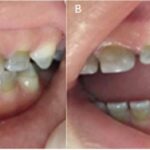

Endodoncia que duele es una pregunta común que nos llevan muchos pacientes que acuden a nuestra clínica buscando una solución a sus dolores dentales. La endodoncia constituye la principal forma de tratamiento para remediar los daños causados por caries en los dientes; sin embargo, este proceso siempre genera muchas interrogantes entre los pacientes, principalmente, acerca de si duele realizar dicho tratamiento. ¿Qué tenemos que decir sobre esto?

Una endodoncia es el tratamiento cuya finalidad es eliminar el tejido pulpar (o vital) dañado. Es en este punto donde se encuentran las raíces y los nervios del diente. En términos básicos, la endodoncia consiste en limpiar el interior del diente y sustituir la zona afectada por materiales sintéticos para proteger el diente restante.